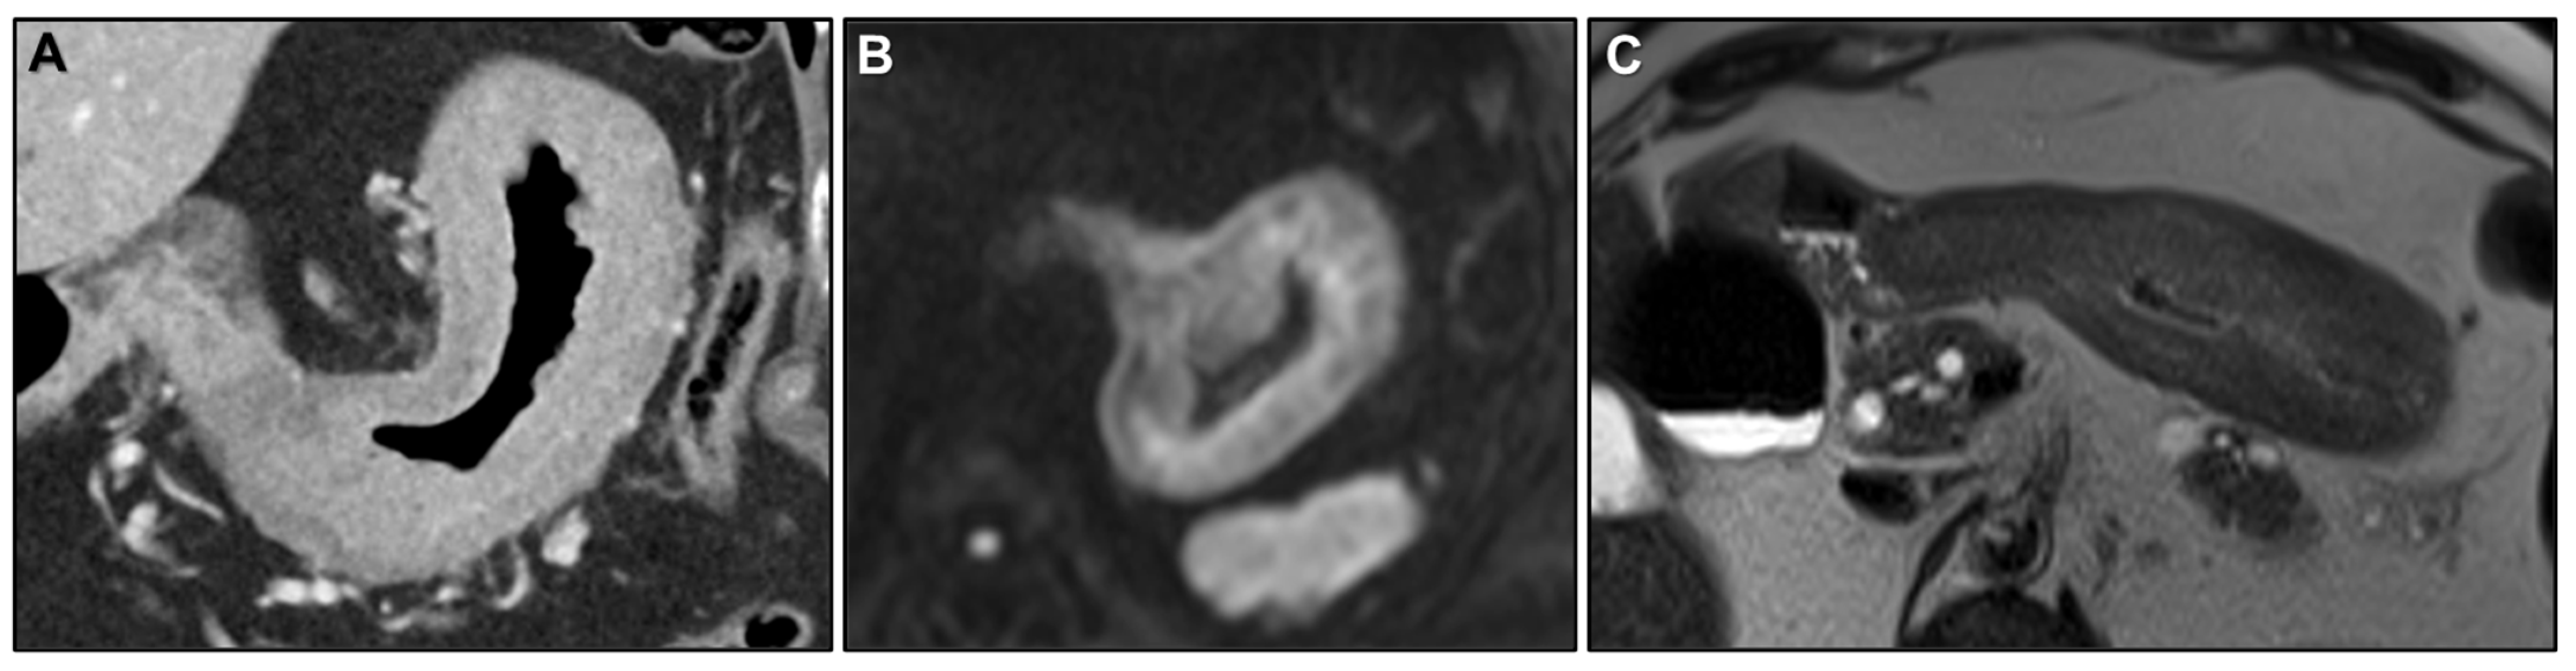

Presacral Fat Tissue and Rectovaginal Septum Infiltration and T2-Weighted Imaging (T2WI) Hypointense Extramural Tumour Component

- Dresen, R.C.; Beets, G.L.; Rutten, H.J.T.; Engelen, S.M.E.; Lahaye, M.J.; Vliegen, R.F.A.; de Bruïne, A.P.; Kessels, A.G.H.; Lammering, G.; Beets-Tan, R.G.H. Locally advanced rectal cancer: MR imaging for restaging after neoadjuvant radiation therapy with concomitant chemotherapy. Part I. Are we able to predict tumor confined to the rectal wall? Radiology 2009, 252, 71–80. [Google Scholar] [CrossRef]